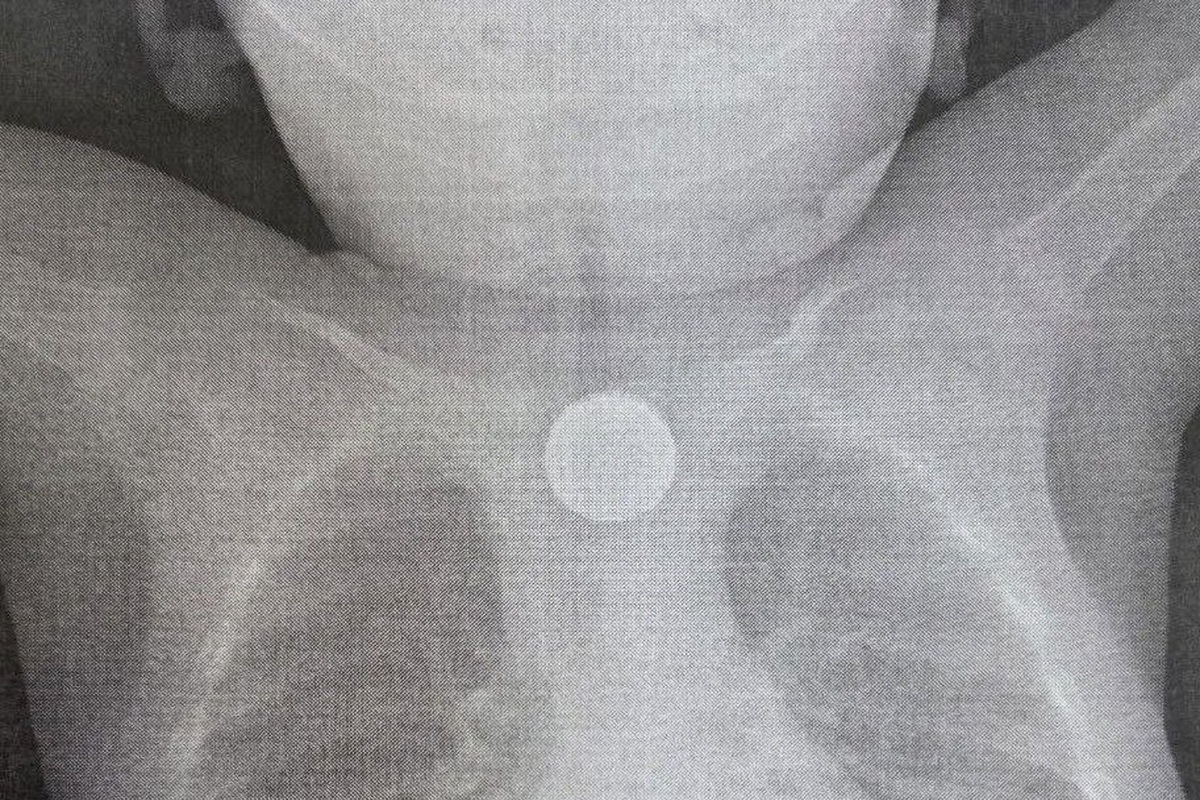

Срочная операция была проведена в Детской республиканской клинической больнице (ДРКБ) в Улан-Удэ, где медики спасли жизнь годовалому пациенту. Малыш проглотил дисковую литиевую батарейку и двухрублевую монету, что привело к тяжелейшему химическому ожогу пищевода.

Поводом для обращения за медицинской помощью стало резкое ухудшение состояния ребенка 27 ноября. У малыша началась многократная рвота, а спустя два часа поднялась температура и появились хрипы при дыхании. После осмотра в центральной районной больнице, где было диагностировано инородное тело в пищеводе, ребенка экстренно направили в ДРКБ, рассказали в учреждении здравоохранения.

Специалисты больницы оперативно провели эндоскопическое вмешательство. Бригада в составе врача-эндоскописта Зорика Хангалова, медсестры-эндоскописта Ларисы Никитиной и анестезиолога-реаниматолога Романа Цвикевича извлекла опасные предметы. Находясь в пищеводе, литиевая батарейка вызвала химический ожог слизистой оболочки третьей степени, создавший прямую угрозу жизни ребенка, подчеркнули в ДРКБ.